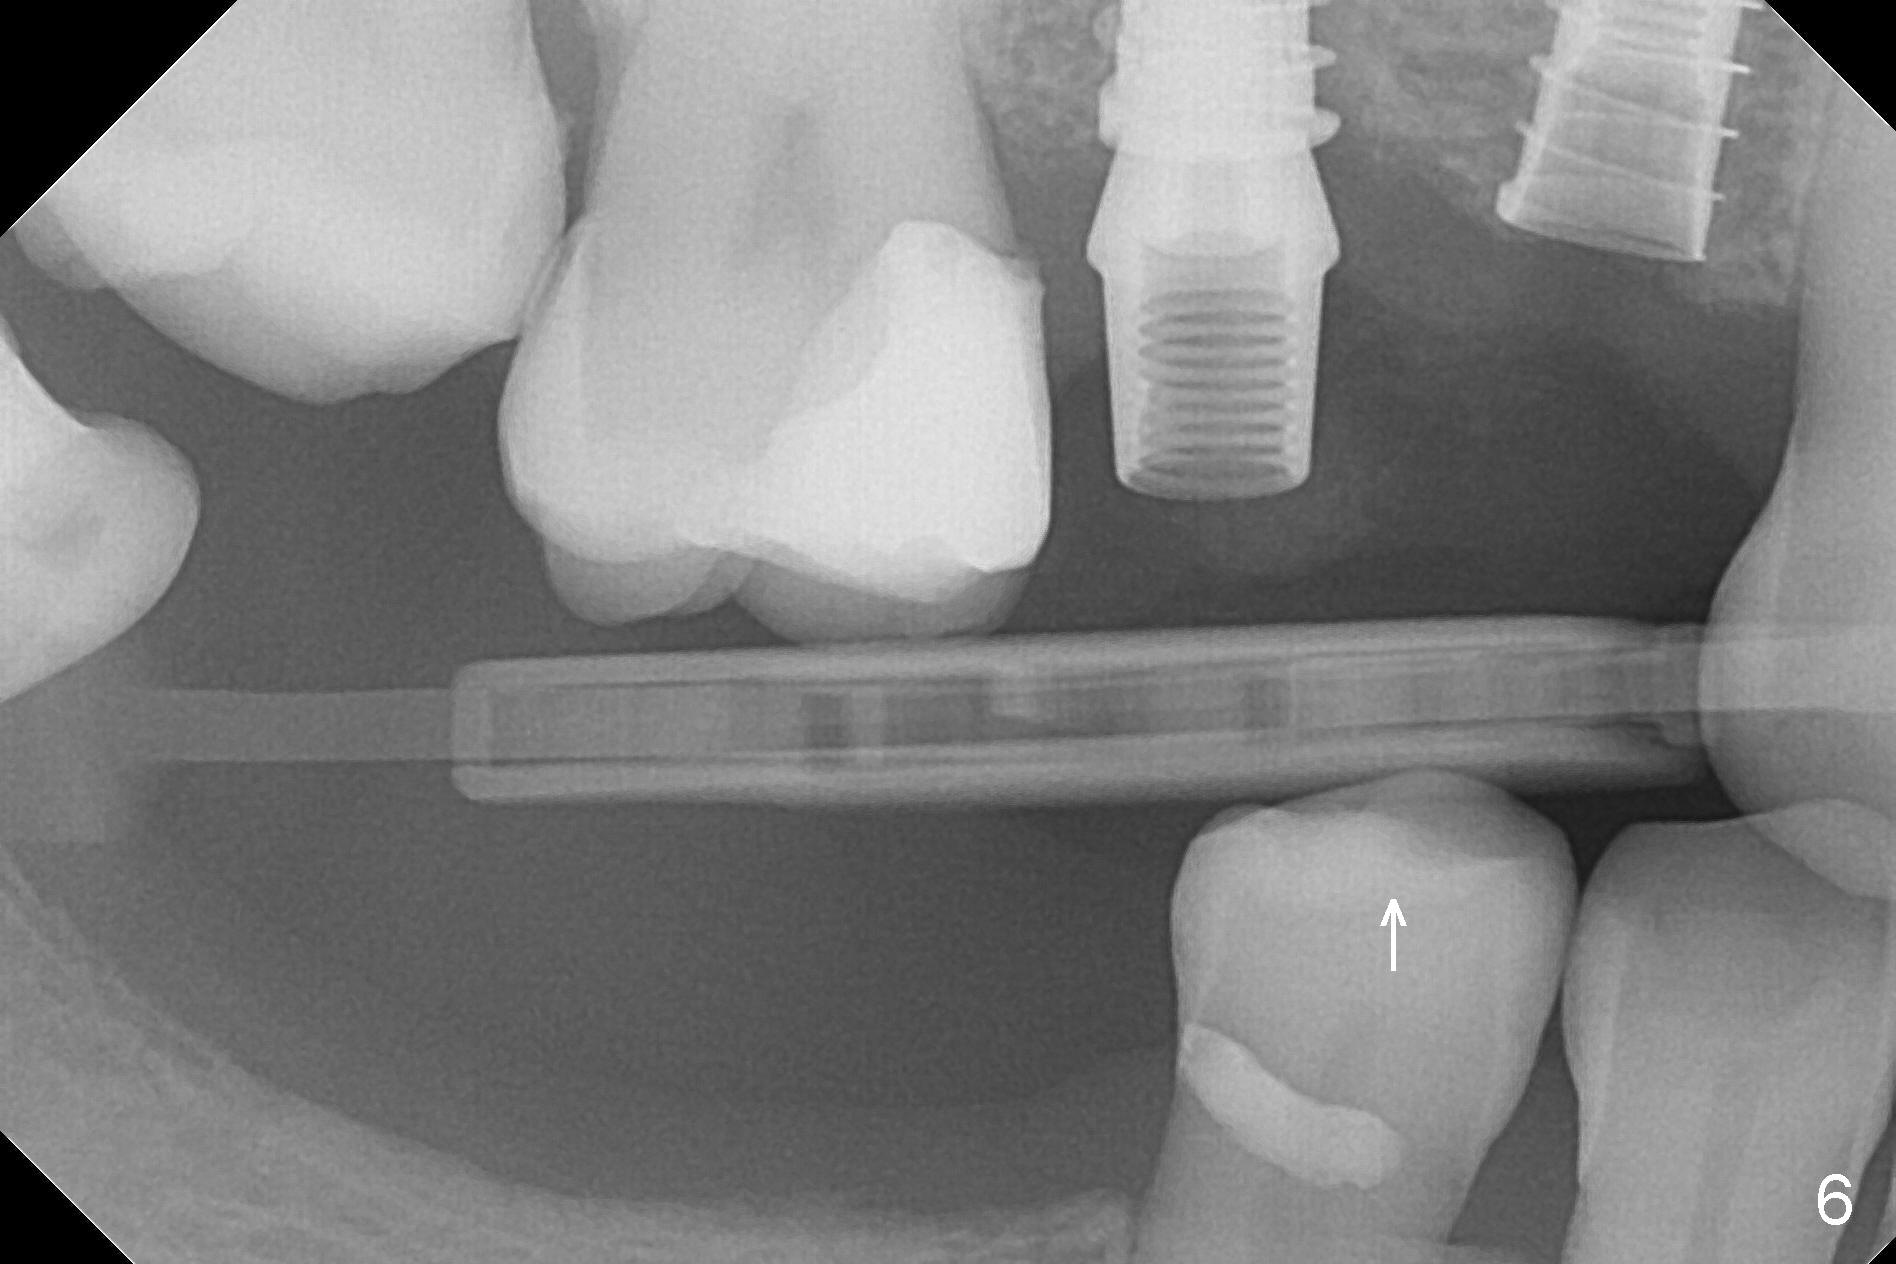

At the healed site (#5), insertion torque of a 4x11 mm implant is >50 Ncm (Fig.4). Because of supraeruption of the tooth #28 (Fig.6 arrow), a healing abutment (4x2 mm) is placed at #5 (data not shown), while a pair abutment (4.5x4(2) mm) is placed at #4 (Fig.4,6). In fact a splinted provisional is placed at #4 and 5 with a low occlusal table. There is no apparent bone loss 1 years 5 months postop (Fig.7). In fact the implants either perforate the palaatal or buccal (B) plate, as revealed by CBCT (1 year 6 months postop, immediately post cementation, Fig.8,9). It appears necessary to have guided surgery and smaller implant in the narrow ridge.